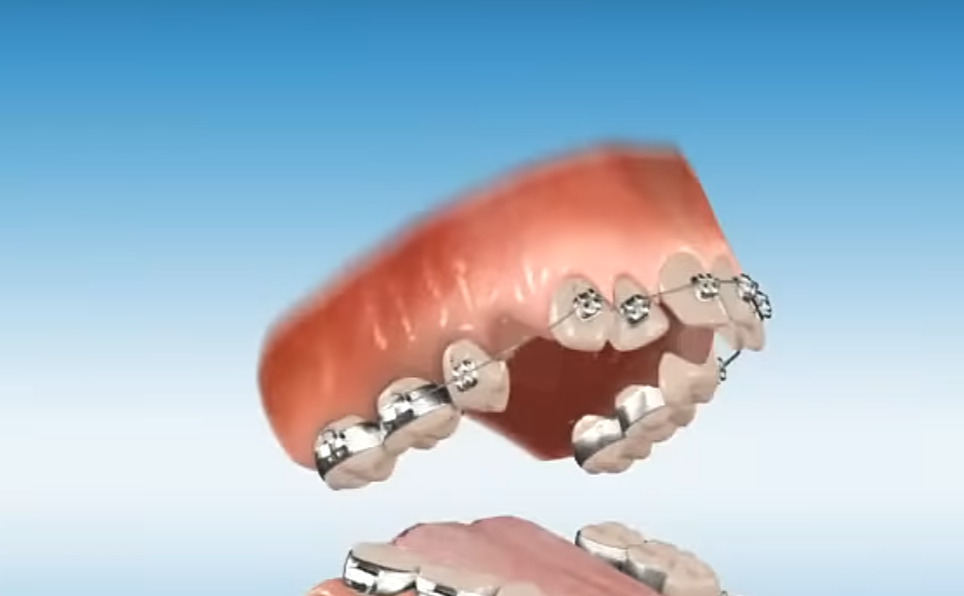

basically if orthodont only removes your UPPER 4th 2 molars will it still recess you? (in overbite case) because i heard people completely have their bone structure fallen because of upper and lower jaw molar extractions. i dont need extractions from both, just 2 4th molars from upper jaw. thanks